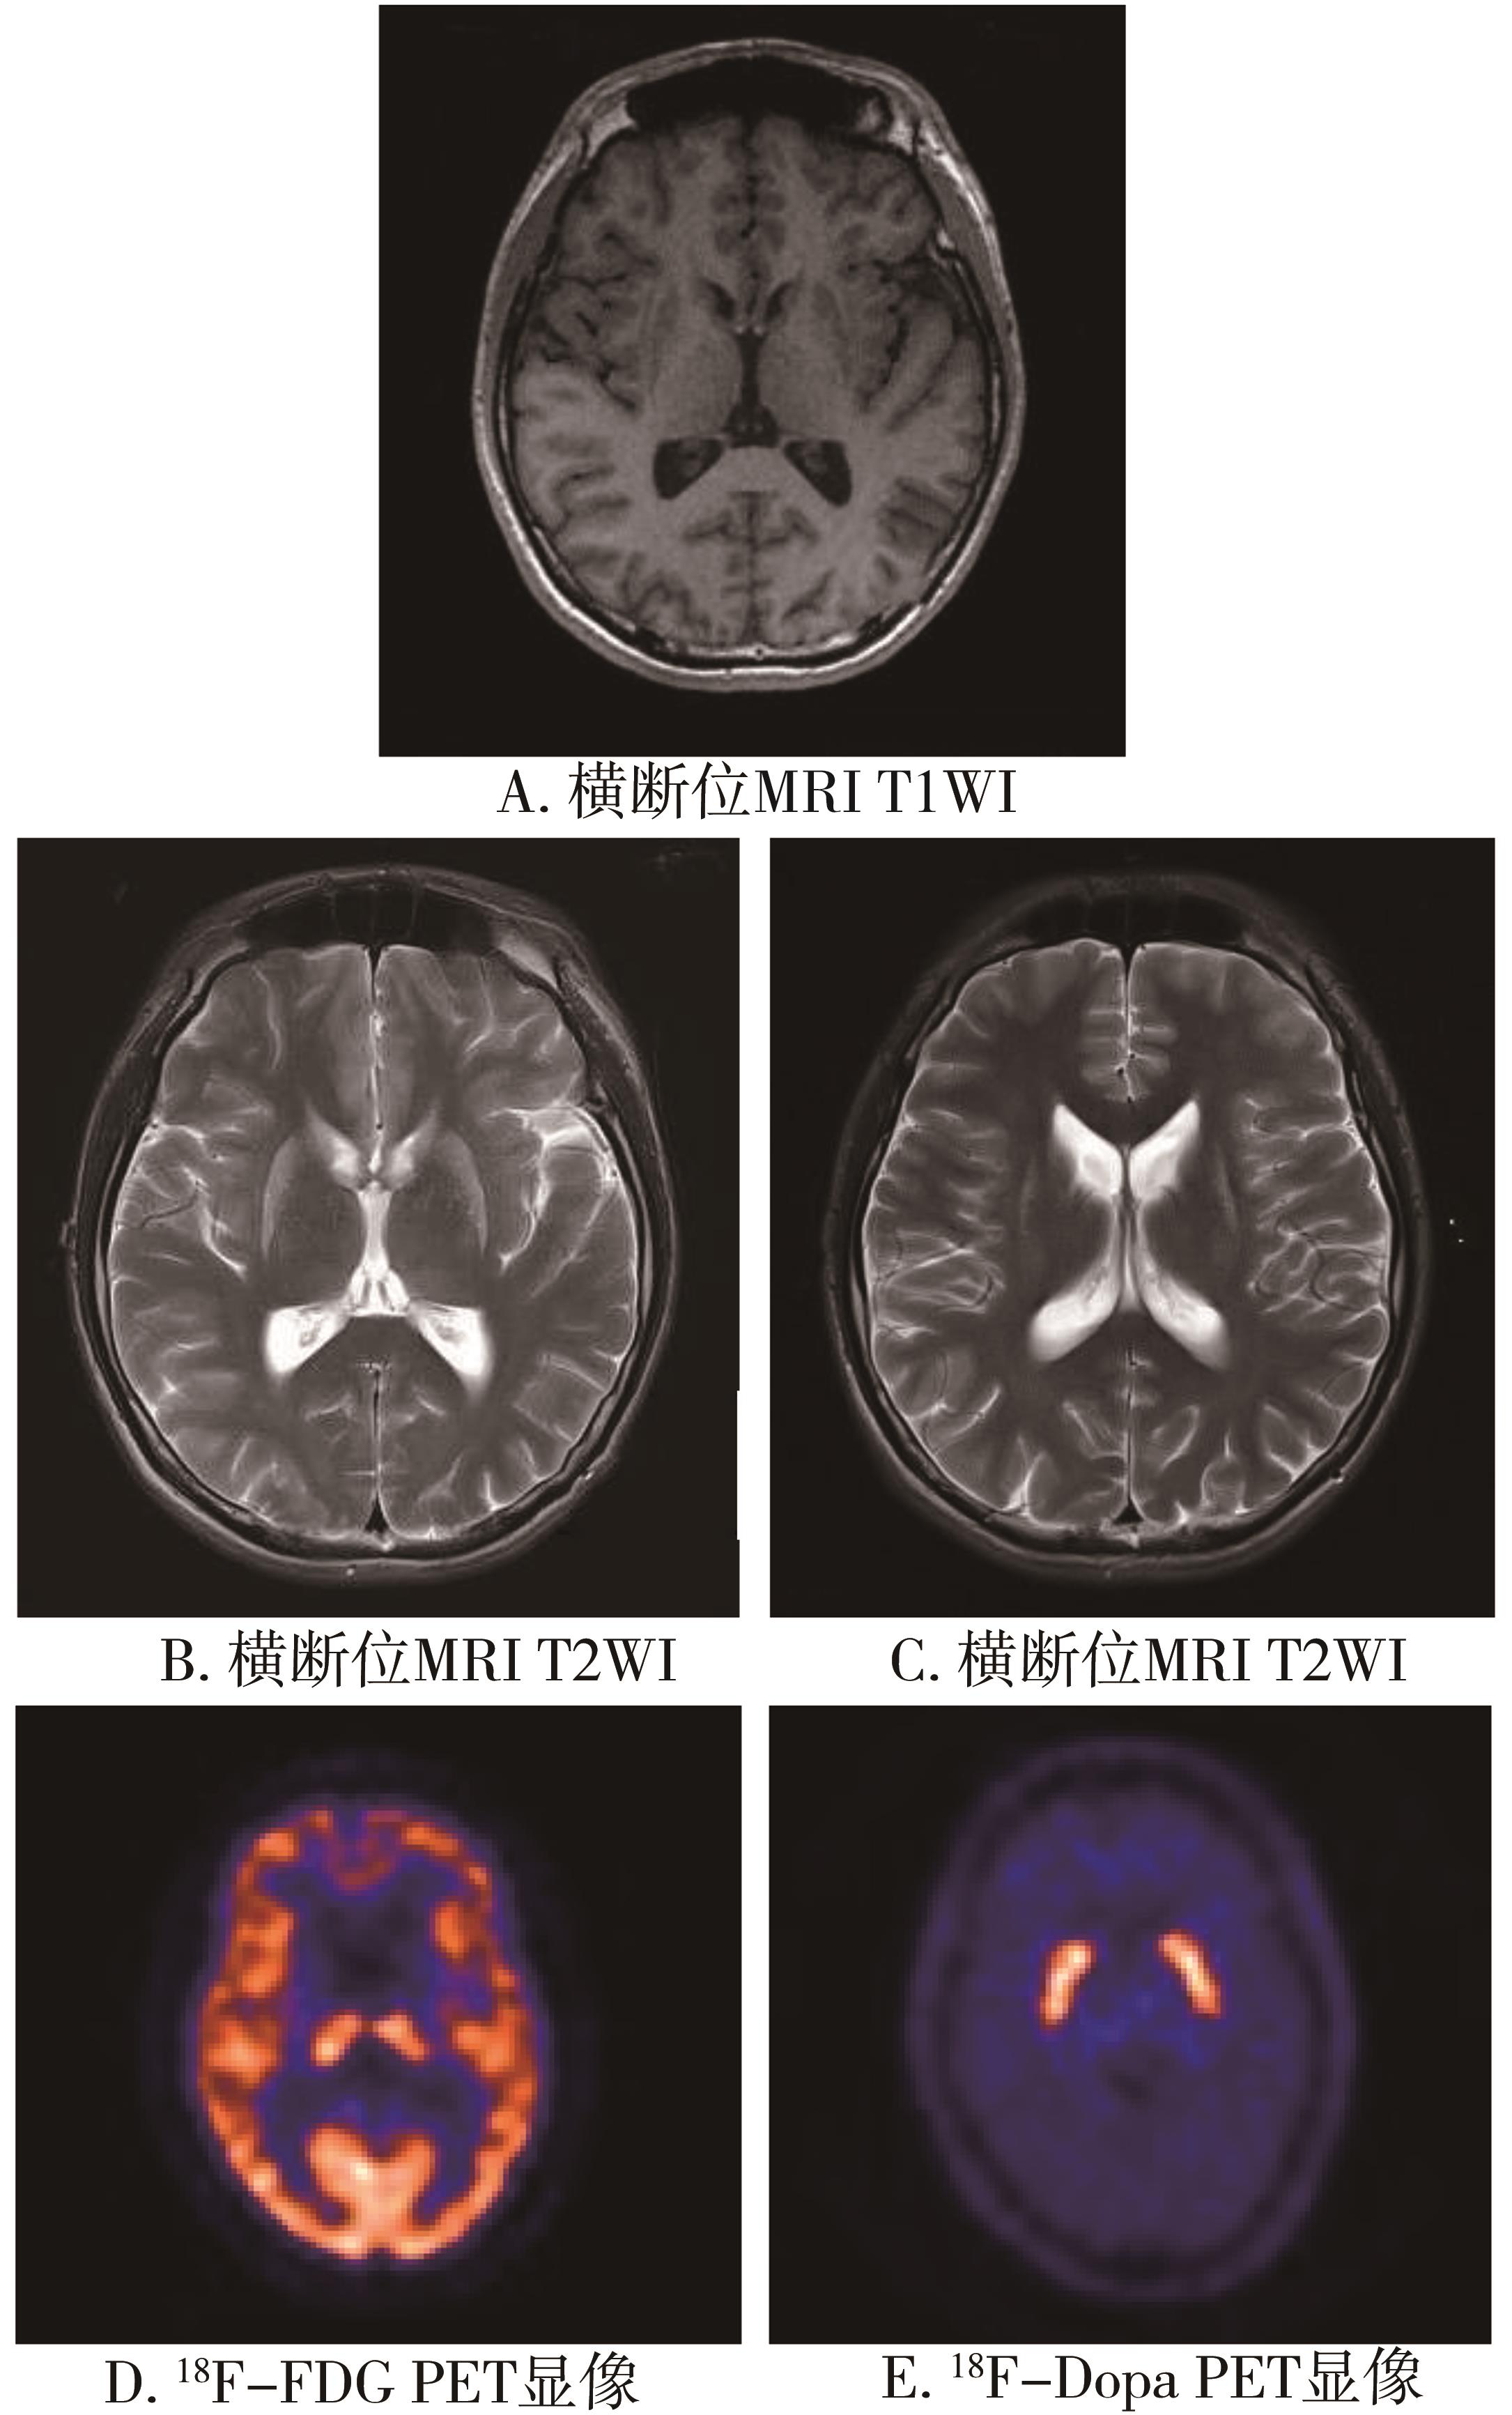

• 舞蹈症-棘红细胞增多症的早期识别和筛查

2022, 47(7):866-870. DOI: 10.13406/j.cnki.cyxb.003039

摘要 (583) HTML (43) PDF 2.07 M (376) 评论 (0) 收藏

摘要:目的 探讨舞蹈症-棘红细胞增多症(chorea-acanthocytosis,ChAc)临床特点,为该病早期诊断提供思路和方法。方法 通过回顾性研究,总结ChAc临床特点。结果 符合舞蹈样运动障碍的患者中,ChAc占29%,确诊时间中位值为5.5年。患者的发病年龄为(33.57±12.23)岁;7例(100%)均有口腔运动障碍,4例(57%)出现癫痫(全面强直阵挛发作),6例(86%)出现腱反射减弱或消失,5例(71%)肌酸激酶增高;头颅磁共振可见尾状核尤其尾状核头(57%)和豆状核(29%)萎缩,侧脑室前角扩大(57%);正电子发射断层显像(positron emission tomography,PET)-电子计算机断层扫描(computed tomography,CT)可见双侧基底节区低代谢表现(43%)。所有患者均可见棘红细胞比例大于3%,基因测序29%可发现责任基因VPS13A突变。结论 ChAc的确诊时间长,口腔运动障碍、肌酸激酶增高有助于尽早识别。建议舞蹈症患者常规进行2次以上的外周血涂片,进而再进行基因检测确立诊断。